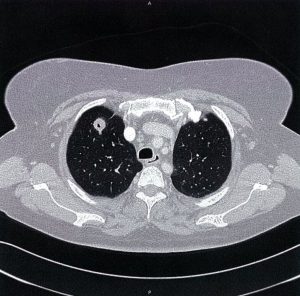

ایسکمی حاد اندام (ALI) یک اورژانس عروقی است که در آن خونرسانی شریانی به یک یا چند اندام به شدت کاهش مییابد. ترومبوز شریانی و آمبولی قلب مسئول اکثر موارد هستند. علائم و نشانههای معمول شامل درد، رنگ پریدگی، کاهش نبض، سردی، فلج و پارستزی اندام است که در قسمت دیستال به محل انسداد ایجاد میشود.